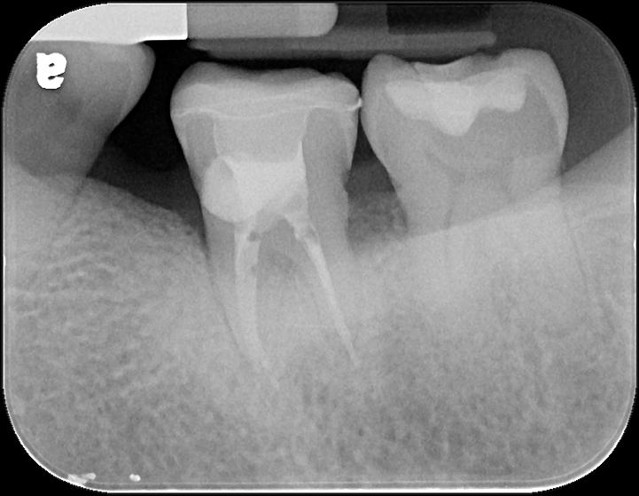

治療前,再次蛀牙,牙齒排列不整

蛀牙已至牙髓

#37-顯微根管治療

治療後X光,密合度良好